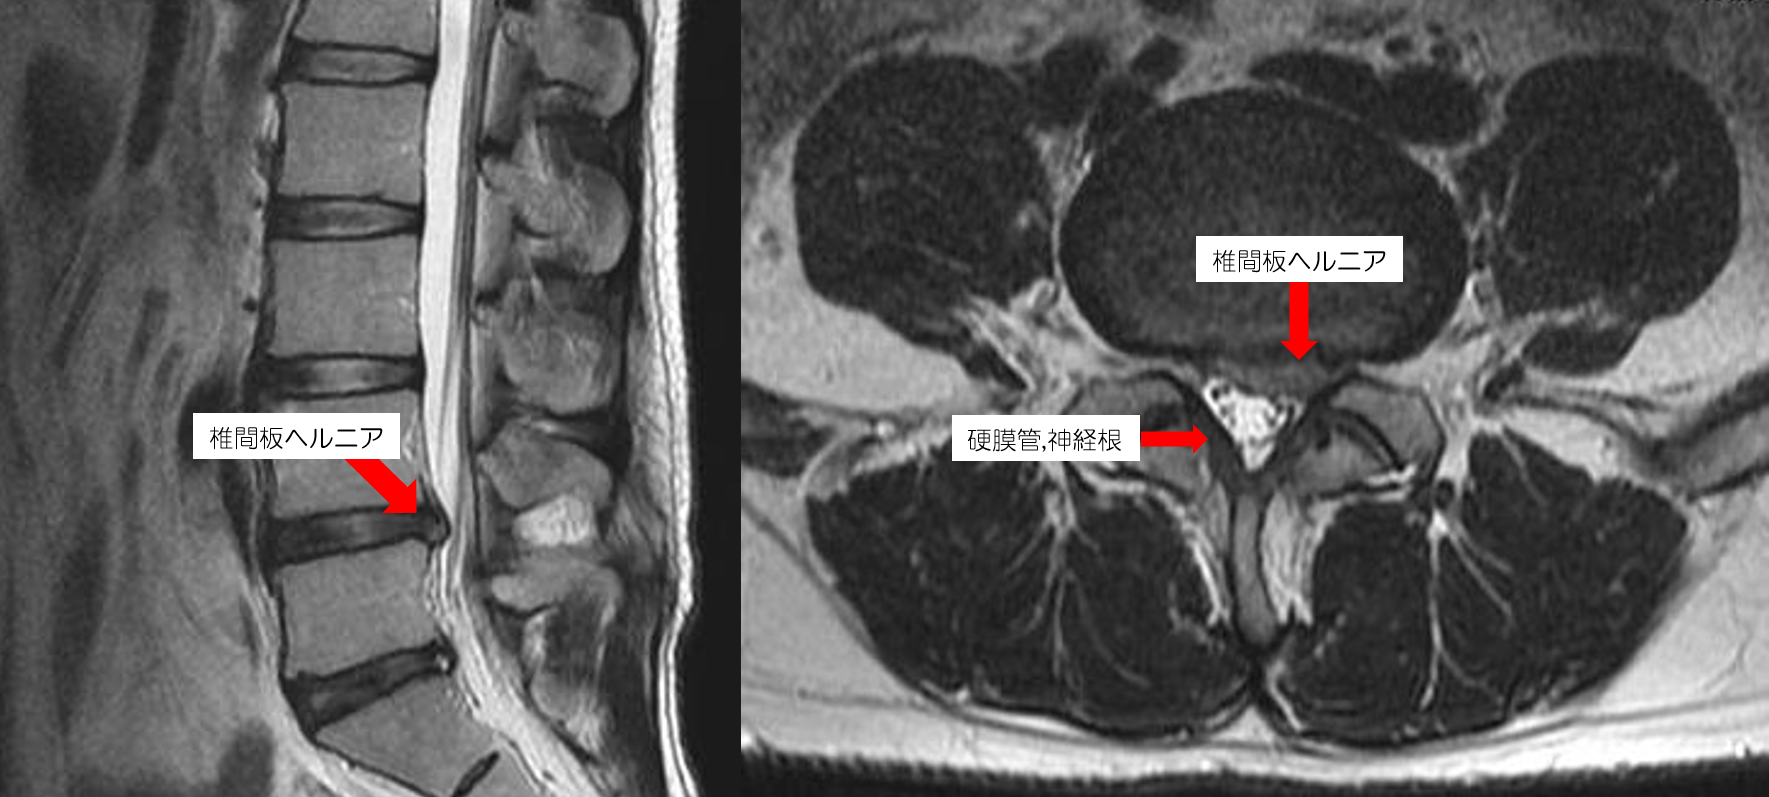

医師は、影響を受けた椎間板を探すために CT スキャンまたは MRI を指示する必要があると考えるかもしれません。ただし、多くの場合、信頼性の高い診断をするには、徹底的な検査と、問題の症状や病歴に関する詳細な質問に答えるだけで十分です。中年になると、MRI では椎間板に異常が見られるようになりますが、痛みやその他の問題は発生しません。